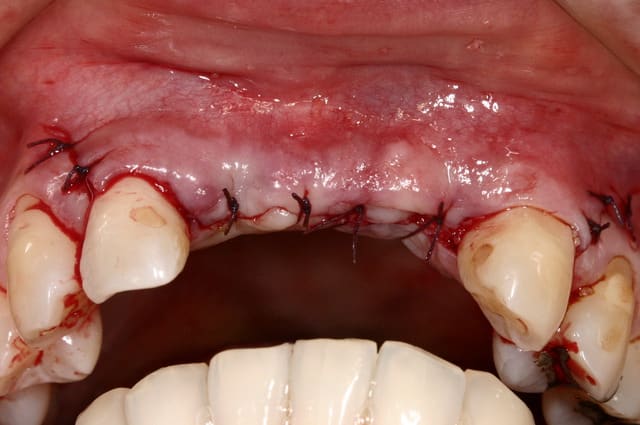

as-tu une photo juste post-op avec les sutures?

je confirme également que les greffons allogéniques biobank cortico-spongieux donnent d'excellents résultats (et en granules également pour ceux qui veulent combler des alvéoles comme il en est discuté sur une autre file)

C'est le cas où j'avais eu exposition de la greffe...

http://www.eugenol.com/sujets/390124-c-est-quoi?page=1

Une exposition du greffon c'est toujours problématique et tu as parfaitement bien géré le problème. Ca n'est jamais gagné d'avance et il est important de le gérer au plus vite si possible dès son apparition.